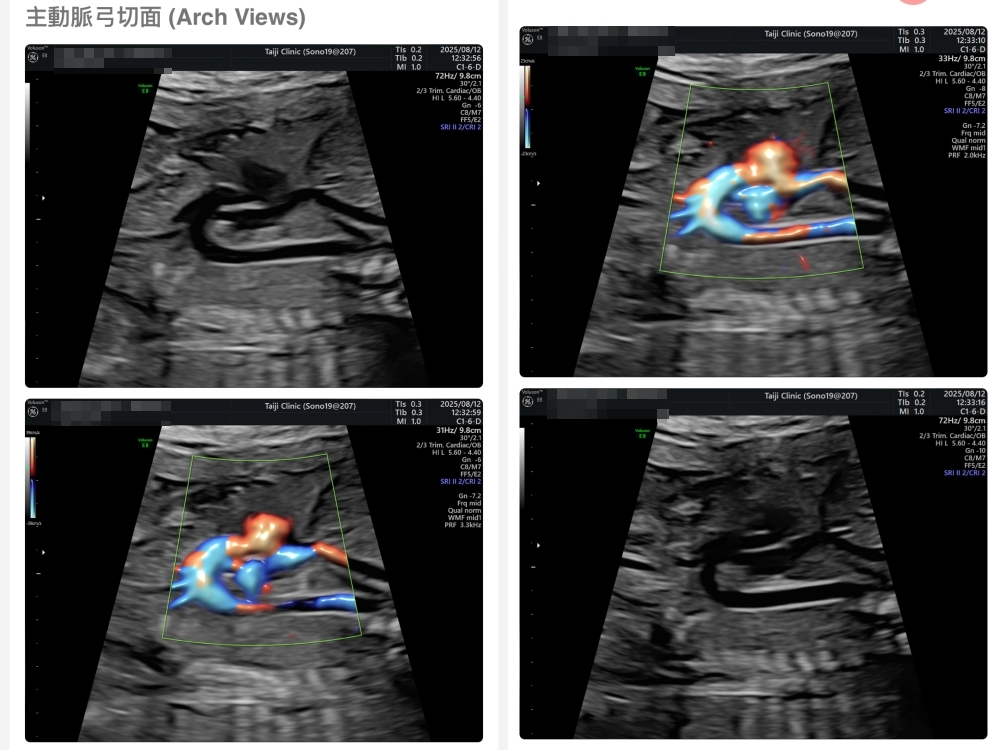

【台兒|高層次超音波|檢查結果】

▲離開診所後會收到MAIL,我們14:05離開,大約是16:45收到mail,裡面會有滿滿的超音波照片,紀錄的很詳細!也會提供紙本的報告,可以給日後產檢的醫師做參考👌